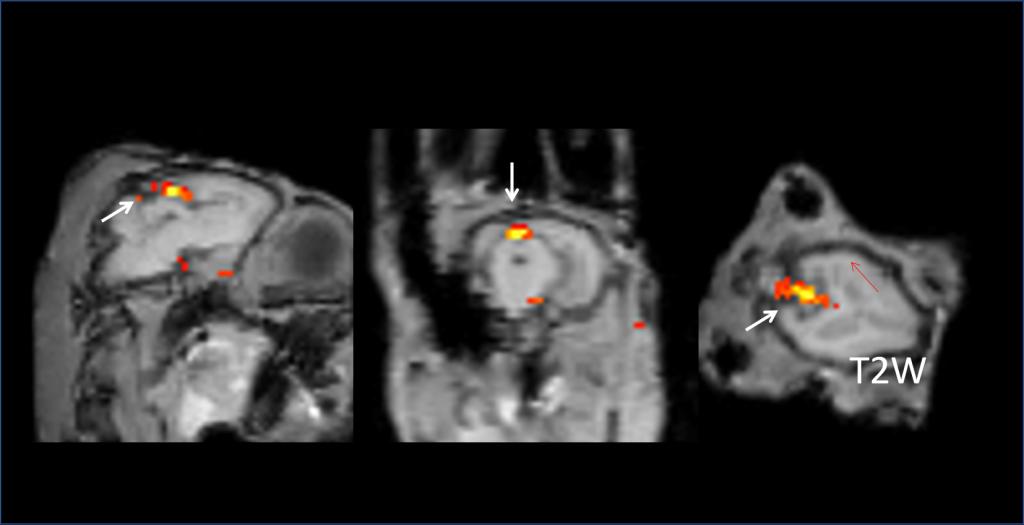

中心的研究团队包括多名医学影像领域的著名科学家和青年骨干,以医学成像和临床应用研究为核心,推动其在中国的发展,并在科技创新、产业结合方面提供多学科全球化的科研、教学和临床服务。影像中心拥有两台先进的3T全身磁共振成像系统(Philips Ingenia CX 3.0T和Siemens Prisma 3.0T),一台超高场5T全身磁共振成像系统(联影 Jupiter 5.0T),多套超声成像系统(含一台ICONEUS 脑功能超声成像系统),以及配套的成像技术、软硬件开发平台、图像数据处理工具和临床图像处理软件。中心的专业运行和技术支持团队以磁共振平台为核心,面向用户提供优秀的基础科学研究、成像技术研发和临床医学转化服务。

影像中心自成立以来,承担了科技部、国家自然科学基金委、卫生部、北京市科委等近百项国家和省部级项目,收到各种研究经费支持达5000万余元,已发表论文600余篇,发明专利60余项,国际专利10余项,培养学生130余人,获得各种奖励30余项。影像中心已成为全球重要的医学影像尤其是磁共振技术研发中心,开发出大视野高分辨血管壁多对比度成像、三维心肌定量成像、定量血流成像、定量生理成像、无变形高分辨率弥散成像等诸多原创技术,同时这些技术被广泛地应用在多项大规模临床人群队列研究当中形成了针对心脑血管、神经变性性疾病等原创性影像学解决方案。